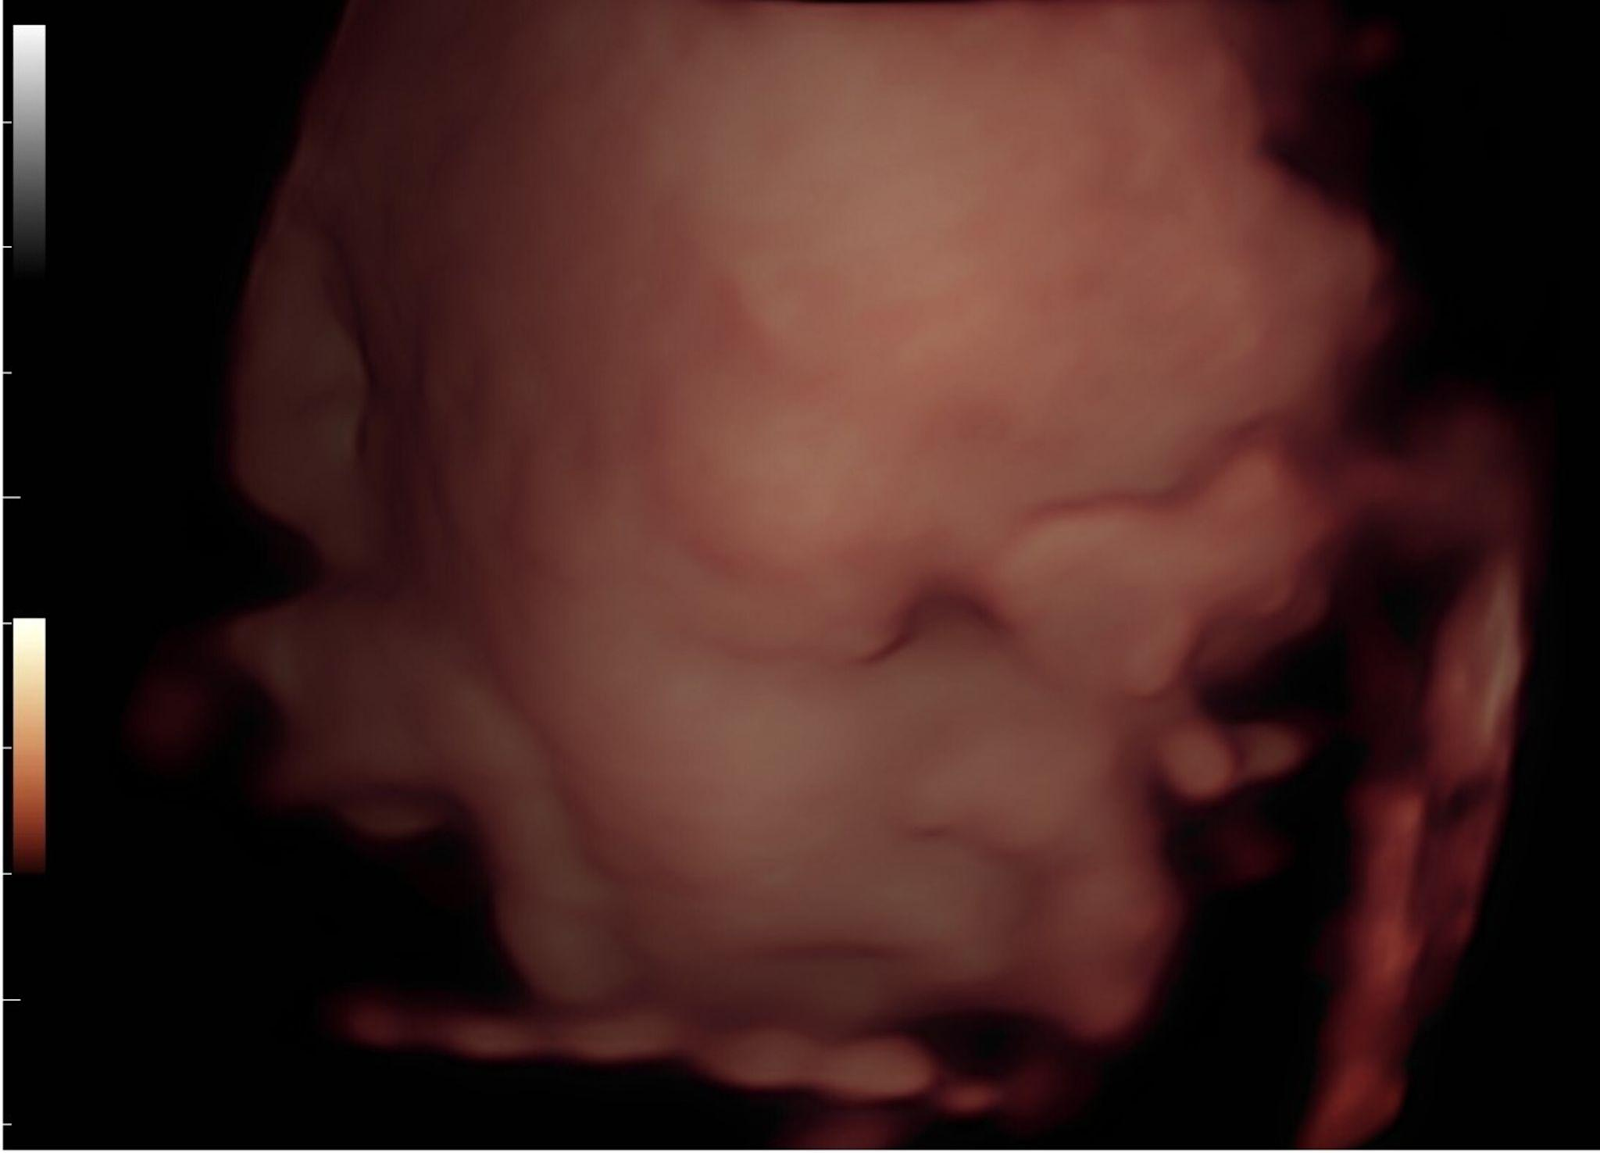

A ecografia 3D é um exame de imagem que utiliza ultrassons para criar imagens tridimensionais do bebé ainda no útero. Ao contrário da ecografia 2D, que apresenta imagens planas em preto e branco, a versão 3D permite visualizar o bebé com maior profundidade, detalhe e realismo.

Este tipo de ultrassonografia 3D na gravidez possibilita observar características físicas como o formato do rosto, mãos, pés e até expressões faciais, e proporciona uma experiência mais envolvente para os pais.

Um dos maiores atrativos da ecografia 3D na gravidez é a qualidade das imagens. A tecnologia permite visualizar o bebé com um nível de detalhe impressionante,o que torna possível identificar traços faciais e até perceber com quem se parece.